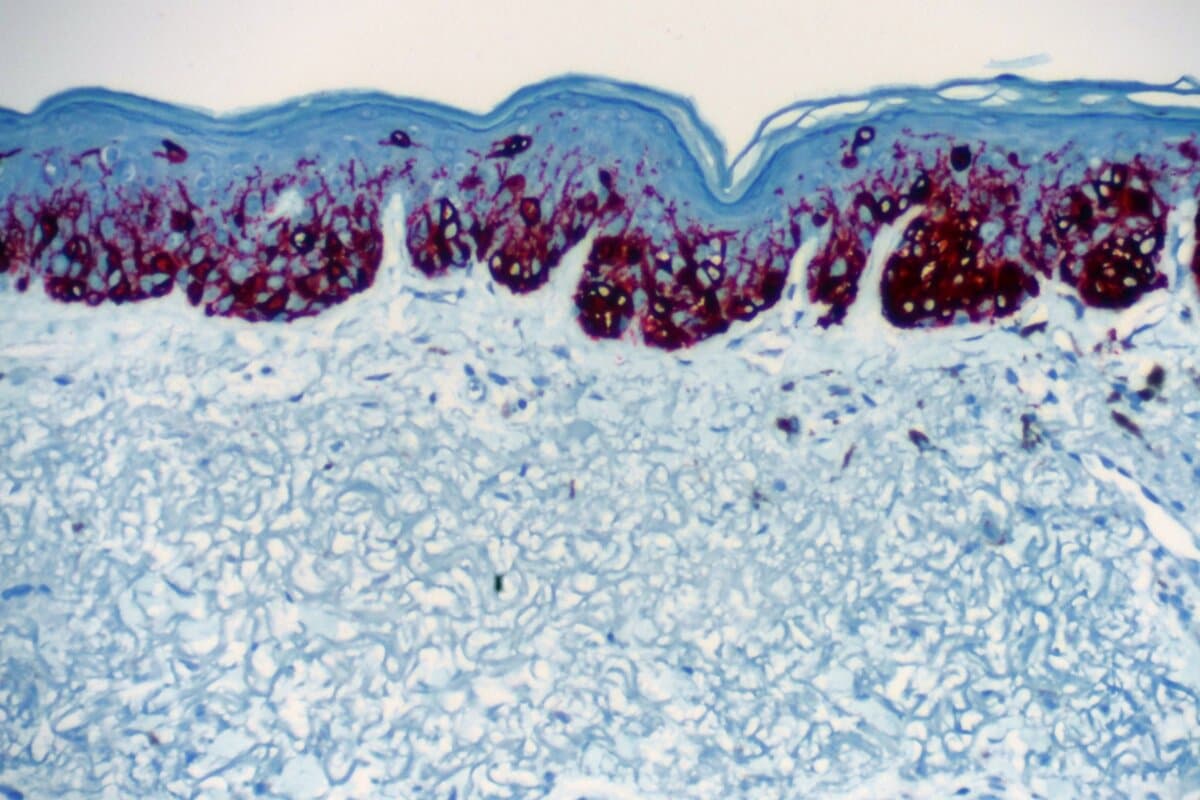

Angiologische Erkrankungen gehören zum Praxisalltag in der Hausarztmedizin – umso wichtiger ist es, Warnsignale früh zu erkennen. Eine strukturierte klinische Untersuchung, einfache Tests und gezielte Diagnostik bei der Abklärung von Gefäßerkrankungen helfen hierbei.